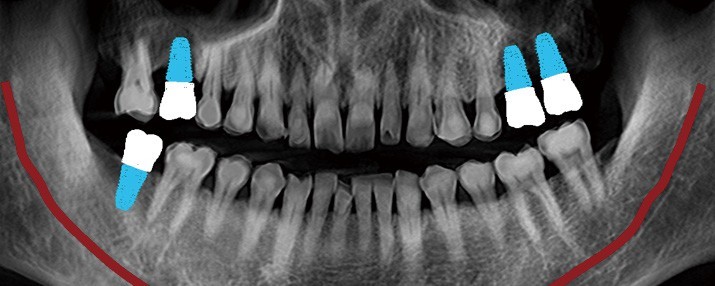

Planificarea implantului asistată de Inteligență Artificială (AI)

Rainbow™ CT integrează funcții avansate de Inteligență Artificială pentru a automatiza și simplifica sarcinile de rutină. De la identificarea poziției dinților lipsă până la stabilirea poziției inițiale a implantului și coroanei, AI-ul Dentium asigură o planificare eficientă și precisă a tratamentelor.

Implant/Coroană: Inteligența Artificială Dentium detectează automat poziția dinților lipsă și stabilește poziția inițială a implantului și coroanei pentru a simplifica planificarea implantului.

Arcada: Algoritmul AI generează automat linia arcadei în doar câteva secunde, cu o precizie ridicată.